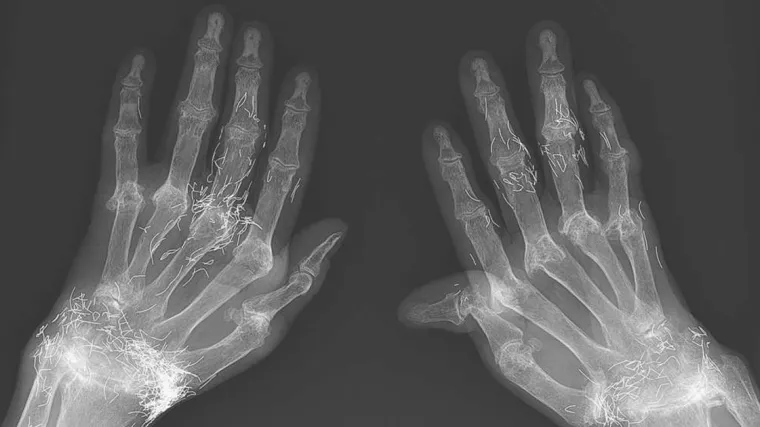

Nakon što je već 40 godina trpjela bolove u rukama 58-godišnja žena iz Južne Koreje konačno je otišla u kliniku za reumatologiju. Osim kroničnog bola u zglobovima šake, prsti su joj bili potpuno izobličeni. Nakon razgovora s liječnicima priznala je kako je još kao tinejdžerica počela koristiti tradicionalnu medicinu koja je trebala olakšati bol, no pravi šok liječnicima uslijedio je nakon što su rendgenom snimili šake, prenosi Unilad.

Na snimci se jasno vidi niz zlatnih iglica koje su umetnute u sve zglobove.

U pitanju je oblik akupunkture u kojoj se akupunkturnom iglom u tijelo trajno postavljaju sterilne zlatne iglice.

Nakon detalje analize slučaja, liječnici su zaključili kako zlatne iglice ipak nisu izravno pogoršale stanje, no oslanjanje na tradicionalnu medicinu ipak je skupo koštalo ženu osobito zato što su se prvi simptomi javili u prilično mladoj dobi.

"Da je u ranim fazama dobila prikladnu liječničku pomoć i tretman, praćen antireumatskim lijekovima umjesto akupunkuture, vjerojatno bi izbjegla deformacije prstiju koje je izazvao reumatidni artritis", zaključuju liječnici.